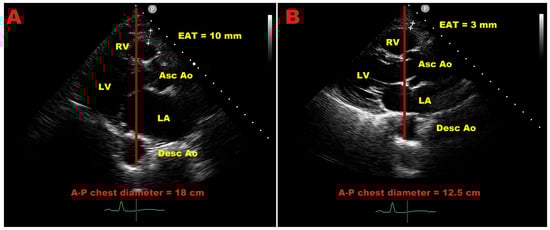

Systolic Versus Diastolic Echocardiographic Assessment of Epicardial Adipose Tissue for the Detection of Obstructive Coronary Artery Disease: A Systematic Review and Meta-Analysis

by Andrea Sonaglioni, Giulio Francesco Gramaglia, Gian Luigi Nicolosi, Massimo Baravelli and Michele Lombardo

Background: Epicardial adipose tissue (EAT) is a metabolically active visceral fat depot increasingly associated with the development and progression of coronary artery disease (CAD). Transthoracic echocardiography is the most widely used modality for EAT assessment; however, substantial heterogeneity exists regarding the timing [...] Read more.

Background: Epicardial adipose tissue (EAT) is a metabolically active visceral fat depot increasingly associated with the development and progression of coronary artery disease (CAD). Transthoracic echocardiography is the most widely used modality for EAT assessment; however, substantial heterogeneity exists regarding the timing of measurement within the cardiac cycle, with EAT thickness variably assessed during systole or diastole. Whether these measurements provide equivalent information for identifying obstructive CAD remains unclear. This systematic review and meta-analysis evaluated the association between echocardiographically measured EAT thickness and angiographically confirmed obstructive CAD, with specific focus on systolic versus diastolic assessments. Methods: PubMed, Scopus, and EMBASE were systematically searched through December 2025 for observational studies comparing EAT thickness in patients with and without obstructive CAD confirmed by invasive coronary angiography. Random-effects models were used to pool standardized mean differences (SMDs) for systolic and diastolic EAT thickness. Heterogeneity was assessed using the I2 statistic, publication bias by funnel plots and Egger’s regression test, and robustness by meta-regression and leave-one-out sensitivity analyses. Results: Twenty-two studies including more than 6500 patients were analyzed. Both systolic and diastolic EAT thickness were significantly greater in patients with obstructive CAD than in non-CAD controls. Systolic EAT showed a large, pooled effect size (SMD 1.27; 95% CI 0.96–1.59; p < 0.001), while diastolic EAT demonstrated a similarly strong association (SMD 1.59; 95% CI 1.10–2.07; p < 0.001). Heterogeneity was substantial (I2 > 90%), but the direction of effect was consistent across all studies. Meta-regression analyses indicated that demographic, clinical, metabolic, geographic, and methodological characteristics, including ultrasound software/vendor category and timing of EAT measurement, did not significantly moderate the association between EAT thickness and obstructive CAD. No significant publication bias was detected, and sensitivity analyses confirmed the robustness of the results. Conclusions: Echocardiographically measured EAT thickness is strongly and consistently associated with obstructive CAD, irrespective of whether measurements are obtained during systole or diastole. Although both approaches show robust discriminatory capacity at the population level, differences in effect magnitude suggest that they may not be fully interchangeable. Moreover, in the absence of standardized and broadly applicable cut-off values, the interpretation and clinical management of EAT measurements as individual risk predictors require further investigation. Full article